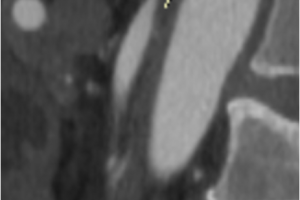

Хирургами центра сосудистой хирургии им. Т.Топпера выполнена уникальная операция по лечению синдрома абдоминальной ишемии у пожилого мужчины с тяжелой сопутствующей патологией. При поступлении пациент предъявлял жалобы на боль в животе, постоянного характера, потерю веса на 27 кг за последние 6 месяцев, отсутствие аппетита. При обследовании выявлены стенозы чревного ствола, верхней брыжеечной артерии и окклюзия нижней брыжеечной артерии, а также трофические изменения в желудке и тяжелое заболевание крови.

Хирурги центра сосудистой хирургии им. Т.Топпера, под руководством Светликова А.В., выполнили операцию по восстановлению кровотока в органах желудочно-кишечного тракта, соответствующую всем Мировым стандартам. Операция была проведена под местной анестезией через кожную пункцию (без разрезов). Боль в животе начала стихать на операционном столе, а полностью прошла в течении часа. На 8 сутки после эндоскопического контроля (ФГДС), на котором была отмечена положительная динамика, пациент был выписан на амбулаторное лечение.